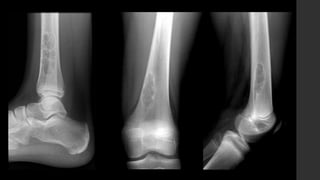

Fibroma no osificante.

• RX y CT

 Típicamente son circunscritos, asimétricos, lesiones radiolúcidas corticales con un anillo esclerótico.

 Frecuentemente son multiloculadas.

 Se localizan en la metáfisis, adyacente a la fisis.

 Cuando el paciente crece, parece que migra lejos del núcleo de crecimiento.

 No hay reacción perióstica asociada.

• IRM 

 Apariencia variable, depende de la etapa del desarrollo e involución de la lesión.

 Inicialmente la lesión muestra señal alta en T2 con anillo periférico con señal baja.

 Mientras madura la lesión muestra disminución de señal en todas las secuencias.

 Realce variable.